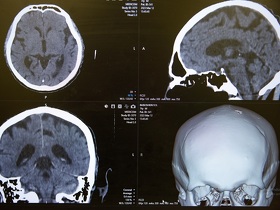

Які ознаки деменції, як швидко вона розвивається та як допомогти близькій людині в боротьбі з нею? Дізнайтеся про це з нашої публікації.

Чому виникає та які наслідки для організму людини може мати менінгіт, як не пропустити тривожні симптоми та вчасно звернутися по допомогу. Дізнайтеся з цієї публікації.